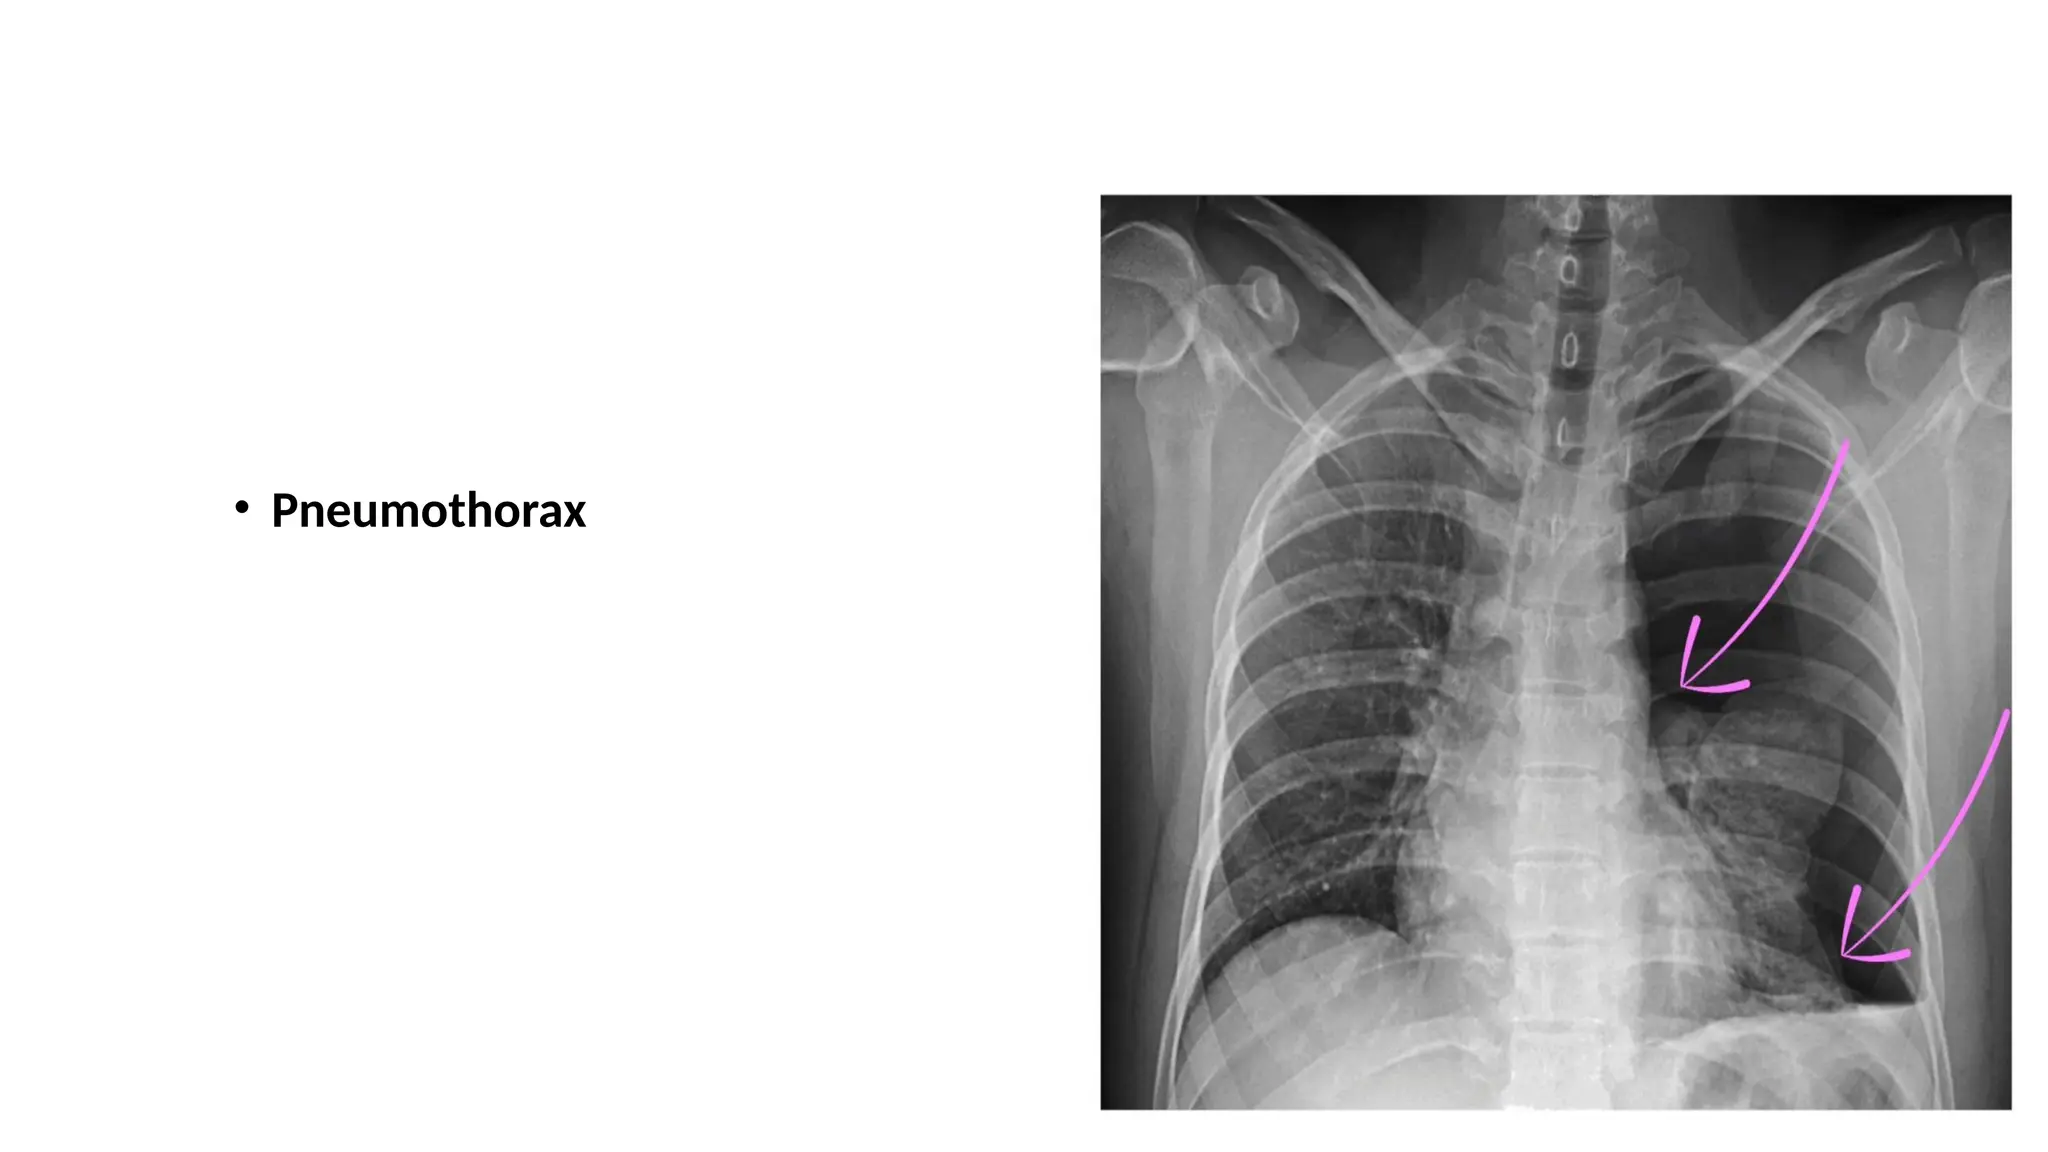

Pneumothorax

Pneumothorax

• Pneumothorax